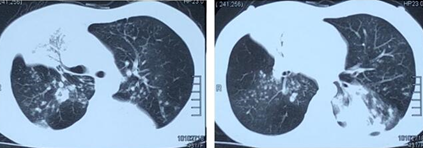

治疗10天后再次复查胸部CT:左下肺病灶范围较前明显增大,同时右肺上叶后段、下叶背段新发斑点状渗出、实变影(图6)

图片

图6  患者胸部CT

患者呼吸困难症状逐渐较前加重。由于患者既往肺活检曾提示肺炎伴机化性改变,且第二次入院后感染相关指标均阴性,并对于再次的强效广谱抗感染治疗无反应,因此考虑患者肺部新发病灶为非感染性,譬如SOP(尽管病理未能发现典型病灶)。遂停止抗感染方案,改为静滴甲强龙40 mg qd。治疗1周后复查胸部CT示病灶较前明显吸收(包括原有吸收不充分的右肺上中叶实变)(图7),遂安排出院后继续口服醋酸泼尼松片20 mg qd。

图7  患者胸部CT